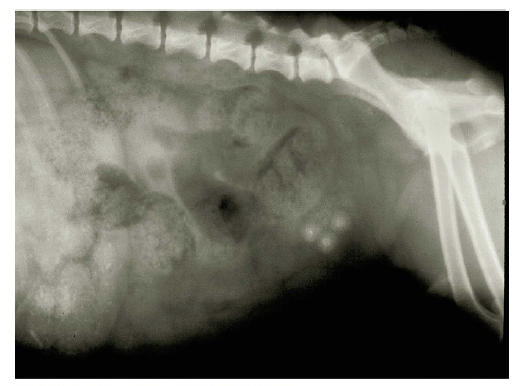

If you are concerned that detail might be lost by excessive reduction, there are several ways you might avoid this. Seldom do you need the whole photograph, right out to all four edges. Therefore, crop the photograph to include only the important part. Commonly, photographs are cropped digitally. If you are submitting a print, you can write “crop marks” on the margin to show where the photograph should be cropped. Figures 18.1 and 18.2 show photographs with and without cropping.

If you can’t crop down to the features of special interest, consider superimposing arrows or letters on the photographs, as shown in Figure 18.3. In this way, you can draw the reader’s attention to the significant features. Having arrows or letters to refer to can aid in writing clear, concise legends.

With electron micrographs, put a micrometer marker directly on the micrograph. In this way, regardless of any reduction (or even enlargement) in the printing process, the magnification factor is clearly evident. The practice of putting the magnification in the legend (for example, x 50,000) is not advisable, and some journals no longer allow it, precisely because the size (and thus magnification) is likely to change in printing. And, usually, the author forgets to change the magnification at the proof stage.

In other photographs where the size of the object is important, likewise include a scale bar. Sometimes showing a familiar object, such as a paper clip, near the object can help readers discern an object’s size. Remember, though, that some objects (such as coins of given denominations) that are familiar to readers in one country might be unfamiliar to readers elsewhere.